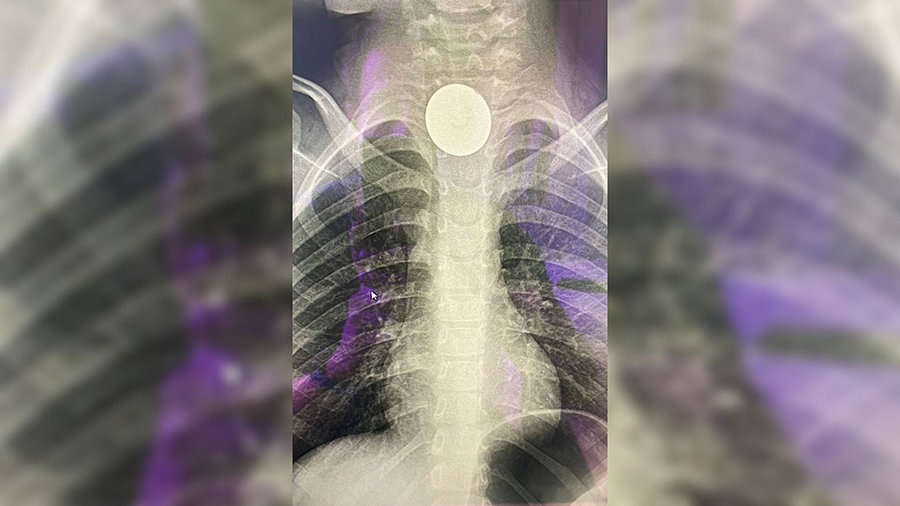

Когда в один из дней у мальчика поднялась температура, его госпитализировали в больницу имени Филатова. Несмотря на то, что у мальчика было подозрение на инфекционное заболевание, врачи сразу заподозрили, что маленький пациент мог что-то проглотить. Сделав рентгенографию пищевода они увидели монету. Инородное тело вызвало воспаление и мешала проходимости пищи.